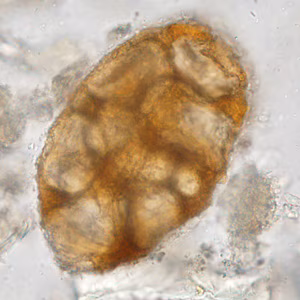

A 42-year-old man with a history of living abroad in Peru for a year returned home to the United States. He reported to his health care provider that he had been experiencing vague intermittent abdominal discomfort. A stool specimen was collected and processed for ova-and-parasite (O&P) examination. Figures A–E show what was observed at 400x magnification in moderate numbers; Figures A and B are of the same object in different focal planes. The object in Figure D is approximately 33 micrometers in diameter. What is your diagnosis? Based on what criteria?

Figure A

Figure B